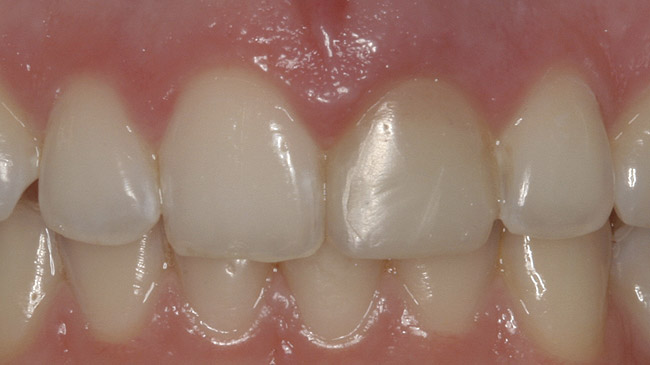

A 36-year-old nonsmoking Caucasian woman in good health presented to the author’s periodontal practice to replace tooth No. 26 with an implant. She had presented to her restorative dentist with a chief complaint of yellow, poorly color-matched mandibular anterior teeth (Figure 1). Her medical history was significant for asthma and seasonal allergies for which she took oral montelukast, orally inhaled fluticasone and salmeterol, and oral cetirizine; she also took lorazepam for anxiety. Her dental history was significant for traumatic experiences.

Figure 1  Initial presentation with yellow, poorly color-matched restored mandibular anterior teeth.

Figure 1